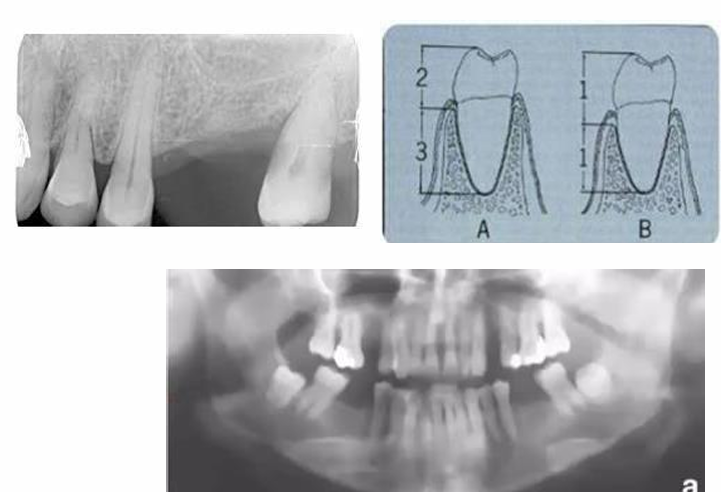

MFD EXAMS /23 6 1234567891011121314151617181920212223 You have 30 min to complete this exam. The timer will start once you begin Attention: Only a few minutes left! Please submit your answers soon. MFD 1 Get a quick sneak peek before the real exam !This trial quiz is designed to show you the question style, difficulty level, and how the options will appear on the platform. 1 / 23 1. What is the lethal dose and toxic dose of fluoride, management? Check 2 / 23 2. What the advantage of silver diamine over other methods and disadvantages ? Check 3 / 23 3. Method of topical fluoride application with concentration ? Check 4 / 23 4. What will happen if left untreated? Check 5 / 23 5. What changes that will happen if the habit stopped? Check 6 / 23 6. Give 3 of your initial stage of treatment? Check 7 / 23 7. What are the causes? Check 8 / 23 8. What is this? Check 9 / 23 9. Then they specified the type of pain and asked about the diagnosis Check 10 / 23 10. What other tests to check vitality of the pulp? Check 11 / 23 11. What are the factors will govern the Rx of Posterior cross bite ? Check 12 / 23 12. What are the factors that govern the treatment of anterior cross bite? Check 13 / 23 13. Name the appliance that you can use to treat this case? Check 14 / 23 14. Name 3 causes? Check 15 / 23 15. Name the most important clinical diagnostic information you need to know. (check RCSI intensive course )? Check 16 / 23 16. What do you see? Check 17 / 23 17. What is your treatment? Check 18 / 23 18. Name the investigations needed? Check 19 / 23 19. causes for gingival enlargement ? Check 20 / 23 20. What is the common side effect of this drug? Check 21 / 23 21. Name the drug that he may take to treat this condition? Check 22 / 23 22. The patient may have what? Check 23 / 23 23. What is this clinical condition? Check /31 2 12345678910111213141516171819202122232425262728293031 You have 30 min to complete this exam. The timer will start once you begin Attention: Only a few minutes left! Please submit your answers soon. MFD 2 Get a quick sneak peek before the real exam !This trial quiz is designed to show you the question style, difficulty level, and how the options will appear on the platform. 1 / 31 1. Mention 2 fixed space maintainers and 2 removable space maintainers other from mentioned : Check 2 / 31 2. Other space maintenance used for child lost primary second molar E before the eruption of the permanent molars ? Check 3 / 31 3. What are the difference between nance appliance and Transpalatal arch Check 4 / 31 4. What material used to attach band? Check 5 / 31 5. What instruction you give to patient? Check 6 / 31 6. Name other fixed space maintainer used in upper jaw and mechanism of their action? Check 7 / 31 7. What component of this appliance? Check 8 / 31 8. What is this appliance , for what its used ? Check 9 / 31 9. Treatment? Check 10 / 31 10. Define Abrasion and Erosion? Check 11 / 31 11. What does this picture show? Check 12 / 31 12. what investigations you can do ? Check 13 / 31 13. Drugs can lead to lichenoid reaction Check 14 / 31 14. What extra oral features in “ Lichenoid reaction )? Check 15 / 31 15. What microscopical features of it ( licheonoid reaction )? Check 16 / 31 16. Definitive diagnosis ? Check 17 / 31 17. Mention type of suggested biopsy ? Check 18 / 31 18. Mention 4 differential diagnosis ? Check 19 / 31 19. Mention 4 questions you will ask the patient ? Check 20 / 31 20. Give 4 intraoral decription of what you see ? Check 21 / 31 21. What the other surgery can be performed to make prothesis? Check 22 / 31 22. Can this tooth stand with fixed prothesis? (in the opg )à taken from Malek file ? Check 23 / 31 23. Radiograph of missing multiple teeth consider it according to Antes law? ON which tooth you will make Abutment ? Check 24 / 31 24. What is Antes law? Check 25 / 31 25. What is best one to use as abutment in fixed prosthesis A or B? Check 26 / 31 26. What relevance of this picture? Check 27 / 31 27. What’s complication of doing surgery in this area floor of mouth? Check 28 / 31 28. Other 2 radiograph needed in diagnosis? Check 29 / 31 29. Give 4 differential diagnosis? Check 30 / 31 30. What can you see ? Check 31 / 31 31. What is the name of radiograph? Check Your score is /30 1 123456789101112131415161718192021222324252627282930 You have 30 min to complete this exam. The timer will start once you begin Attention: Only a few minutes left! Please submit your answers soon. MFD 3 Get a quick sneak peek before the real exam !This trial quiz is designed to show you the question style, difficulty level, and how the options will appear on the platform. 1 / 30 1. Treatment? Check 2 / 30 2. Histopathology? Check 3 / 30 3. Differential diagnosis Check 4 / 30 4. Clinical features’? Check 5 / 30 5. Patient said, this lesion is very frequent, why? Check 6 / 30 6. What are the causes for ulcers? Check 7 / 30 7. Patient have other signs like uveitis ,Genital ulcerations which syndrome he had ? Check 8 / 30 8. Name of the lesion ? Check 9 / 30 9. Mention some TMJ movement ? Check 10 / 30 10. Blood supply ? Check 11 / 30 11. Nerve supply ? Check 12 / 30 12. Which muscles close? Check 13 / 30 13. Action of open and open wide? Check 14 / 30 14. Why it’s Atypical joint ? Check 15 / 30 15. Name of the ligaments ? Check 16 / 30 16. What would be your management? Check 17 / 30 17. Bacteria involved Check 18 / 30 18. Which type of Periodontitis? Check 19 / 30 19. Treatment? Check 20 / 30 20. Histopathology? Check 21 / 30 21. Differential diagnosis? Check 22 / 30 22. Clinical features? Check 23 / 30 23. What are the time frames for making a complaint? Check 24 / 30 24. What are the 3 points related to negligence? Check 25 / 30 25. Who is allowed access to the patient records? Check 26 / 30 26. How to differentiate if it is upper or lower motor neuron lesion? Check 27 / 30 27. Management? Check 28 / 30 28. What are the causes? Check 29 / 30 29. What should you advise the patient to do? Check 30 / 30 30. What is this lesion? Check Your score is /24 1 123456789101112131415161718192021222324 You have 30 min to complete this exam. The timer will start once you begin Attention: Only a few minutes left! Please submit your answers soon. MFD 4 Get a quick sneak peek before the real exam !This trial quiz is designed to show you the question style, difficulty level, and how the options will appear on the platform. 1 / 24 1. What does MRONJ stands for? Check 2 / 24 2. Give definition for MRONJ Check 3 / 24 3. For what medical problems these medications are used? Check 4 / 24 4. Stages of MRONJ 3 Check 5 / 24 5. What’s this appliance? Check 6 / 24 6. At what age is it used? Check 7 / 24 7. What type of malocclusion is it used to treat? Check 8 / 24 8. What changes will produce? (4 options) Check 9 / 24 9. Disadvantages? Check 10 / 24 10. Why is it flabby tissue? Check 11 / 24 11. what is this condition called? Check 12 / 24 12. Causes ? Check 13 / 24 13. Clinical Features ? Check 14 / 24 14. How to avoid it ? Check 15 / 24 15. Management? Check 16 / 24 16. Ideal post length and width Check 17 / 24 17. Definition of Ferrule it’s the Check 18 / 24 18. What is the importance of the ferrule effect ? Check 19 / 24 19. Describe the radiolucency? Check 20 / 24 20. Give 6 differential diagnosis? Check 21 / 24 21. Give 5 radiographical features? Check 22 / 24 22. What is the difference between incisional and excisional biopsy? Check 23 / 24 23. What other 2 plain radiographs we can we can take? Check 24 / 24 24. ALARA? Check Your score is /22 1 12345678910111213141516171819202122 You have 30 min to complete this exam. The timer will start once you begin Attention: Only a few minutes left! Please submit your answers soon. MFD 5 Get a quick sneak peek before the real exam !This trial quiz is designed to show you the question style, difficulty level, and how the options will appear on the platform. 1 / 22 1. . Types of external root resorption? Check 2 / 22 2. The cause of root resorption in the pic? Check 3 / 22 3. How you will treat it? Check 4 / 22 4. What is this probe? Check 5 / 22 5. What is the mark a ? Check 6 / 22 6. What is the mark b ? Check 7 / 22 7. What is the score from the given reading? Check 8 / 22 8. What is the treatment need of the patient according to the score? Check 9 / 22 9. What is the differential diagnosis ? Check 10 / 22 10. Four clinical features of the lesion? Check 11 / 22 11. Treatment ? Check 12 / 22 12. Describe what do you see? Check 13 / 22 13. Causes for it ? Check 14 / 22 14. Treatment ? Check 15 / 22 15. Picture of patient with Anaphylaxis…after taking Check 16 / 22 16. What is diagnosis? - Check 17 / 22 17. What a the signs of Anaphyalxis reactions ? Check 18 / 22 18. What first line of treatment? Dose? Route of Adminstration? Check 19 / 22 19. Other drug used? Check 20 / 22 20. What are expected complications if not treated ? Check 21 / 22 21. What precautions should be made to prevent anaphylaxis reaction ? - Check 22 / 22 22. Name 10 drug in emergency used with their route of Administration and their condition they use in? Check Your score is /36 1 123456789101112131415161718192021222324252627282930313233343536 You have 30 min to complete this exam. The timer will start once you begin Attention: Only a few minutes left! Please submit your answers soon. MFD 6 Get a quick sneak peek before the real exam !This trial quiz is designed to show you the question style, difficulty level, and how the options will appear on the platform. 1 / 36 1. . What are cases that you have to extract the primary tooth? Check 2 / 36 2. D. What are the indications for extraction? Check 3 / 36 3. What are your treatment options? Check 4 / 36 4. Investigations? Check 5 / 36 5. Type of trauma? Check 6 / 36 6. Patient diagnosed with sjorgen syndrome Histology ? - Check 7 / 36 7. Patient diagnosed with sjorgen syndrome Mention four blood investigations ? Check 8 / 36 8. Patient diagnosed with sjorgen syndrome Mention two sites where can we take the biopsy Check 9 / 36 9. Patient diagnosed with sjorgen syndrome How can you differentiate between primary and secondary ? Check 10 / 36 10. Gingival inflammation present in which syndrome Check 11 / 36 11. What is the treatment? Check 12 / 36 12. mention another connective tissue disease that can lead to lesions “ intraorally “ similar to the Lichen planus ? Check 13 / 36 13. what serious complication can arise from Erosive lichen planus ? Check 14 / 36 14. If it was atrophic lesion what histology might be seen ? Check 15 / 36 15. List the histological features of lichen planus ? Check 16 / 36 16. Lichen planus what dose it affect? Check 17 / 36 17. Age group commonly affected ? -ref SAQ Check 18 / 36 18. What are the clinical presentation ‘ types of lichen planus ‘ Check 19 / 36 19. What might you see in patient’s body that has a relation to this lesion? Check 20 / 36 20. What are the differential diagnoses? Check 21 / 36 21. Factors for platelet adhesion? Check 22 / 36 22. What can you see? Check 23 / 36 23. Other 2 process of hemostasis? Check 24 / 36 24. Two diseases in which they increase ? Check 25 / 36 25. Two diseases in which they decrease? Check 26 / 36 26. Medical term when they decrease? And if they increased Check 27 / 36 27. Function Check 28 / 36 28. Life span ? Check 29 / 36 29. From where they arise? Check 30 / 36 30. Normal number? Check 31 / 36 31. What are the function of the guiding plane ? Check 32 / 36 32. The success rate ? Check 33 / 36 33. Mention single extra preparation requirement for Resin bonded bridge in posterior teeth ? Check 34 / 36 34. Mention 5 preparation features of it? Check 35 / 36 35. Give two advantages of it ? Check 36 / 36 36. What’s the name of this prosthesis? Check Your score is /23 1 1234567891011121314151617181920212223 You have 30 min to complete this exam. The timer will start once you begin Attention: Only a few minutes left! Please submit your answers soon. MFD 7 Get a quick sneak peek before the real exam !This trial quiz is designed to show you the question style, difficulty level, and how the options will appear on the platform. 1 / 23 1. If the same scenario but the tooth is subluxated. What is the management? Check 2 / 23 2. Aim of this procedure Check 3 / 23 3. Steps to do this procedure? Check 4 / 23 4. Management? How to asses the vitality of the tooth Check 5 / 23 5. Mention factors that can affect the treatment plan ? Check 6 / 23 6. Identify the Kenneyd’s classification Check 7 / 23 7. Name its parts? Check 8 / 23 8. Uses of Surveyor Check 9 / 23 9. What is this ? Check 10 / 23 10. Criteria for hand piece sterilization Check 11 / 23 11. steps for wrapped instrument sterilization process ( ref : sterilization in SDCEP)? Check 12 / 23 12. What is the difference between sterilization and decontamination? Check 13 / 23 13. Optimal temperature & pressure & time for autoclave? Check 14 / 23 14. Difference between vacuum and non-vacuum autoclave in mechanism? Check 15 / 23 15. Optimum temperature? Check 16 / 23 16. Advantage of vaccum over non vaccum? Check 17 / 23 17. What is the significance of forehead wrinkling? Check 18 / 23 18. What is Ramsy haunt syndrome ? Rx ? and is it LMN or UMN ? Check 19 / 23 19. Enumerate 3 extracranial and intracranial causes for this ? Check 20 / 23 20. What are the branches of facial nerve? Check 21 / 23 21. Why do we suture the eye in a patient with Facial Palsy? Check 22 / 23 22. Differentiate between Upper and Lower Motor Neuron lesions? Check 23 / 23 23. What is shown in photograph? Check Your score is /27 0 123456789101112131415161718192021222324252627 You have 30 min to complete this exam. The timer will start once you begin Attention: Only a few minutes left! Please submit your answers soon. MFD 8 Get a quick sneak peek before the real exam !This trial quiz is designed to show you the question style, difficulty level, and how the options will appear on the platform. 1 / 27 1. Mention 4 diseases you would see in HIV Patients? Check 2 / 27 2. Give 2 differential diagnosis for this lesion? Check 3 / 27 3. Describe the lesion shown in Photograph B? Check 4 / 27 4. What is your diagnosis ? Check 5 / 27 5. Describe the lesion shown in Photograph A? Check 6 / 27 6. Disadvantages of gold ? Check 7 / 27 7. Ideal cement for All Porcelain? Check 8 / 27 8. Which cement would u use for high caries risk patient? Check 9 / 27 9. How much would you prepare for functional and non-functional cusps in Gold Crown? Check 10 / 27 10. what crown would you go for in bruxism patients out of these 3? Check 11 / 27 11. Name the 3 restorations? Check 12 / 27 12. After administering Local Anesthesia and deciding the choice of biopsy. What should be done before biopsying the lesion? Check 13 / 27 13. Name 2 systemic steroids with dosage you would recommend for this patient? Check 14 / 27 14. Name 2 topical steroids with dosage you would recommend for this patient? Check 15 / 27 15. What is your diagnosis? Check 16 / 27 16. Describe the lesion shown in photograph? Check 17 / 27 17. Name 5 options to increase retention and stability in class l Check 18 / 27 18. E. What is the function of the RPI system ? Check 19 / 27 19. What are the 2 disadvantages of the 2 restorations you mentioned? Check 20 / 27 20. What materials are your 2 restorations made of? Check 21 / 27 21. Other than implants what restoration would you place in this patient? Check 22 / 27 22. Which Kennedy’s classification is this? Check 23 / 27 23. Describe your management? Check 24 / 27 24. What may be the patient complaint? Check 25 / 27 25. What are the causes of this? Check 26 / 27 26. Describe what you see in the photograph? Check 27 / 27 27. which 4 examinations would you undertake? Check Your score is /31 0 12345678910111213141516171819202122232425262728293031 You have 30 min to complete this exam. The timer will start once you begin Attention: Only a few minutes left! Please submit your answers soon. MFD 9 Get a quick sneak peek before the real exam !This trial quiz is designed to show you the question style, difficulty level, and how the options will appear on the platform. 1 / 31 1. Describe what you see in the photograph? Check 2 / 31 2. Three other features of this syndrome ? Check 3 / 31 3. What is the medical condition associated with it “? Multiple OKC? Check 4 / 31 4. Where expansion occurs in the OKC ? Check 5 / 31 5. From which cells this lesion arises from? Check 6 / 31 6. What is your diagnosis? Check 7 / 31 7. What is the histopathology of the lesion shown in Histology slide? Check 8 / 31 8. Give 4 differential diagnosis? Check 9 / 31 9. What is the consequence of premature loss of deciduous teeth? Check 10 / 31 10. Identify those appliances and mention one use for each and mode of action? Check 11 / 31 11. What component of appliance no. 3 ? Check 12 / 31 12. How to overcome open bite disadvantage ? Check 13 / 31 13. What are Disadvantages of this appliance ? Check 14 / 31 14. What Ceph changes are expected while using this appliance ? Check 15 / 31 15. What is the construction of Twin Block Appliance? Check 16 / 31 16. What skeletal and dental changes are expected while using this appliance ? Check 17 / 31 17. What is the ideal age to treat this condition >? Check 18 / 31 18. Indications of the Twin Block Appliance? Two Check 19 / 31 19. Name the Appliance used to correct this? Check 20 / 31 20. What is the treatment? Check 21 / 31 21. How to prevent it Check 22 / 31 22. Mention three mechanisms of action of Fluoride? Check 23 / 31 23. What is the disease caused by excess Fluoride? Check 24 / 31 24. What are the risk factors associated with this patient? Check 25 / 31 25. Name the principal organism causing this? Check 26 / 31 26. what are the principles of the access cavity Check 27 / 31 27. What is your diagnosis? Check 28 / 31 28. What are principles of cavity preparation? Check 29 / 31 29. What is your Periapical diagnosis? Check 30 / 31 30. What is your Pulpal diagnosis? Check 31 / 31 31. Which test would you undertake? Check Your score is /21 0 123456789101112131415161718192021 You have 30 min to complete this exam. The timer will start once you begin Attention: Only a few minutes left! Please submit your answers soon. MFD 10 Get a quick sneak peek before the real exam !This trial quiz is designed to show you the question style, difficulty level, and how the options will appear on the platform. 1 / 21 1. Patient is 20 years old Mention two treatment options for this case ? Check 2 / 21 2. Patient is 20 years old What is the long term risk for not treating this case ? Check 3 / 21 3. Name of this appliance in the next picture? Check 4 / 21 4. What is the wire used ? Check 5 / 21 5. For which orthodontic cases this appliance is necessary ? Check 6 / 21 6. Why we use retainer ? Check 7 / 21 7. Describe what you see ? Check 8 / 21 8. Differential diagnosis:- Check 9 / 21 9. Name of those muscles ? Check 10 / 21 10. Name the Extrinsic muscles of the tongue? Check 11 / 21 11. . Which nerves innervate the Extrinsic muscles of the tongue?. Check 12 / 21 12. What is the somatic innervation of anterior 2/3 of tongue? Check 13 / 21 13. Which nerve supplies the posterior 1/3 of tongue?. Check 14 / 21 14. From which Pharyngeal arch posterior 1/3 derived from? Check 15 / 21 15. Mention the intrinsic muscle of the tongue ? Check 16 / 21 16. What is the name of this condition ? name the lesion on the skin ? Check 17 / 21 17. Mention 3 drugs that causing it ? Check 18 / 21 18. 2 infections associated with it Check 19 / 21 19. Mention 2 immediate treatment ? Check 20 / 21 20. Why this condition can be fatal ? Check 21 / 21 21. Which test would you undertake? Check Your score is